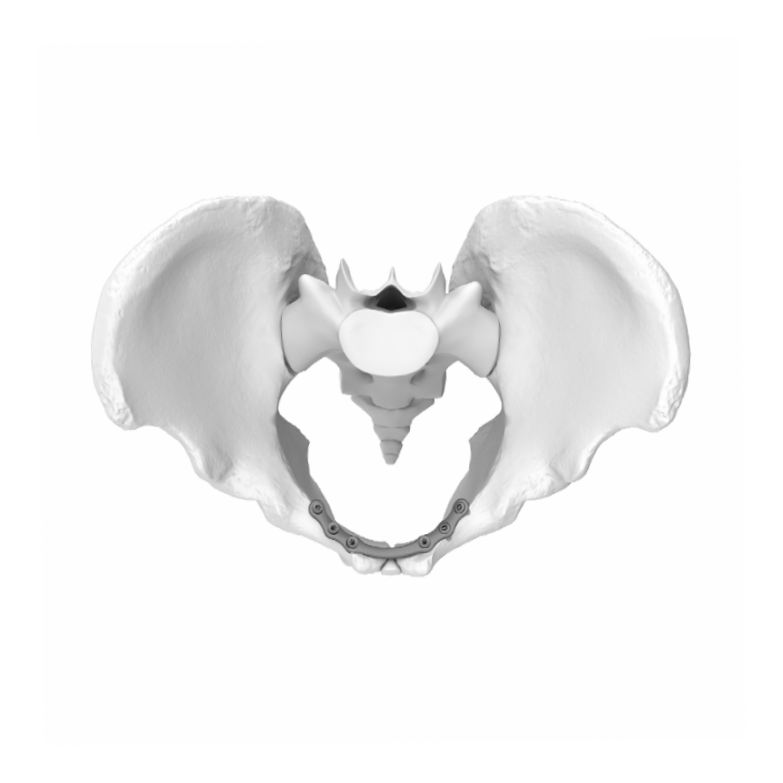

3.5MM Symphyseal Pelvic Plate

The Pelvic Piating Systom is a comprehensive set of piates. screws, and instrumentation designed for fracturta, fusions and astectomies of the acetabulum, sacrum, Bum, and pelvic ring. The Pelvic Plating System can also be used for sacroilac joint dislocations and pubic symphysis disruptions. The implants in the Pelvic Plating System are strategically precontoured where. may save time for the surgeon and left uncontoured where patient anatomy may require porsonal contouring

- Pubic symphysis disruptions

- Pre-contoured Plates.

- Indication-Specific plates are offered, as well as reconstruction-style plates to address a variety of fracture patterns.

- Low profile and rounded edges: Reduce the risk of soft tissue irritation